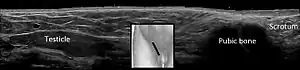

Scrotal ultrasonography of undescended testis: (a) Normal testis in the scrotum (b) Atrophic and decreased echogenicity of the contralateral testis of the same patient seen in the inguinal region

In the minority of cases with bilaterally nonpalpable testes, further testing to locate the testes, assess their function, and exclude additional problems is often useful. Scrotal ultrasound or magnetic resonance imaging performed and interpreted by a radiologist can often locate the testes while confirming absence of a uterus. At ultrasound, the undescended testis usually appears small, less echogenic than the contralateral normal testis and usually located in the inguinal region. With color Doppler ultrasonography, the vascularity of the undescended testis is poor.